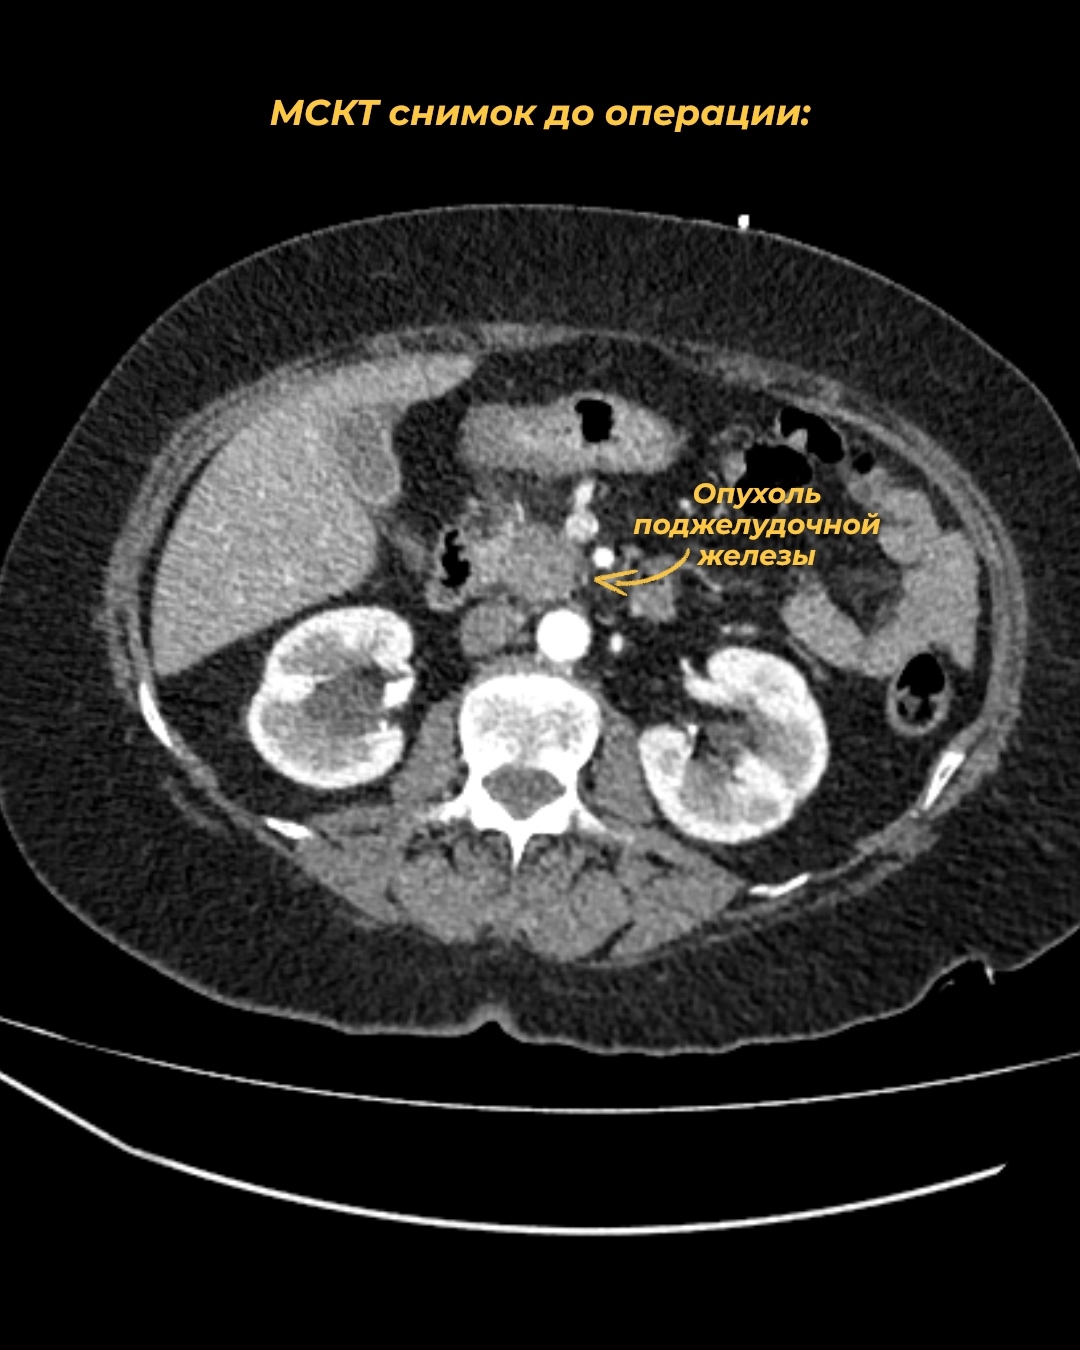

69-летняя пациентка заметила у себя пожелтение кожи и сразу обратилась к врачу в поликлинику. Оттуда ее направили в онкодиспансер с подозрением на опухоль головки поджелудочной железы. Диагноз подтвердился.

На первом этапе врачи устранили угрозу жизни – желтуху: под местным обезболиванием доктора успешно выполнили дренирование внутрипеченочных желчных протоков. Вскоре после этого на мультидисциплинарном консилиуме было решено провести сложнейшую панкреатодуоденальную резекцию (ПДР) – это основное лечение при раке поджелудочной железы.